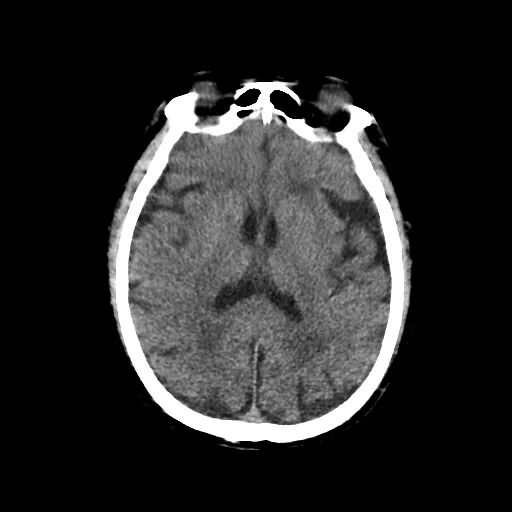

幸运的是,梅爷爷从发病到神经科医生接诊,耗时不到 1 个小时,仍处于卒中后最佳治疗时间窗内,医院立即开启脑卒中救治绿色通道,优先安排化验及颅脑 CT 检查,排除脑出血,明确诊断为「急性脑梗死」。

术前 CT 图